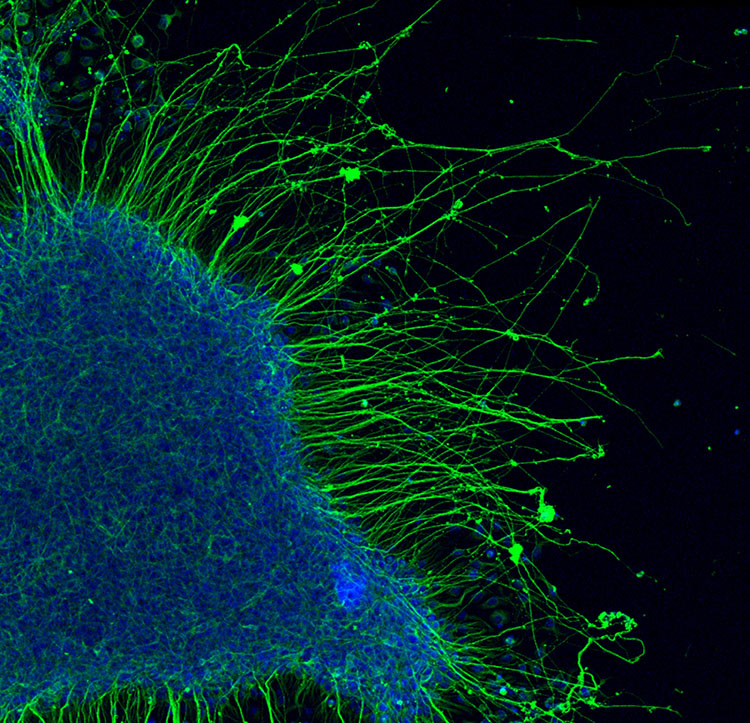

Tissue engineering and regenerative ophthalmology is a field that has been making remarkable strides in recent years, revolutionizing the way we treat eye diseases and injuries. Using cutting-edge technologies and innovative approaches, researchers in this field are developing advanced materials, biocompatible scaffolds, and bioactive molecules that can help restore vision and repair damaged eye tissues. From corneal transplants and retinal implants to stem cell therapies and gene editing, the possibilities in tissue engineering and regenerative ophthalmology are truly awe-inspiring. With its potential to improve the quality of life for millions of people worldwide, it's no wonder that this field is considered one of the coolest and most exciting areas of research today.

Regenerative Cellular Therapies

Stem Cell Derived Retinal Organoids